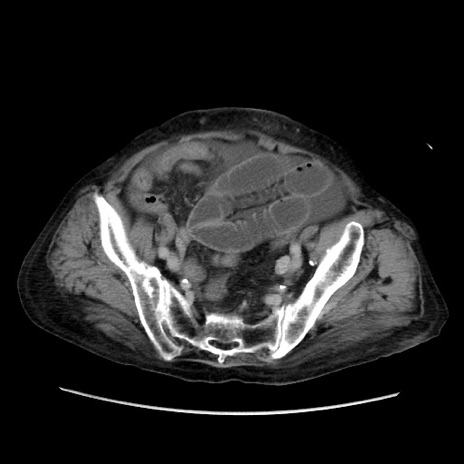

冠状断像